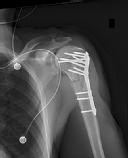

Figure 1 is the radiograph of a 49-year-old man who sustained a closed injury to his

left shoulder in a motor vehicle collision. He underwent uncomplicated ORIF (see Figure 2), but at his first post-operative visit he had persistent pain and deformity (see Figure 3). What is the primary factor contributing to this complication?